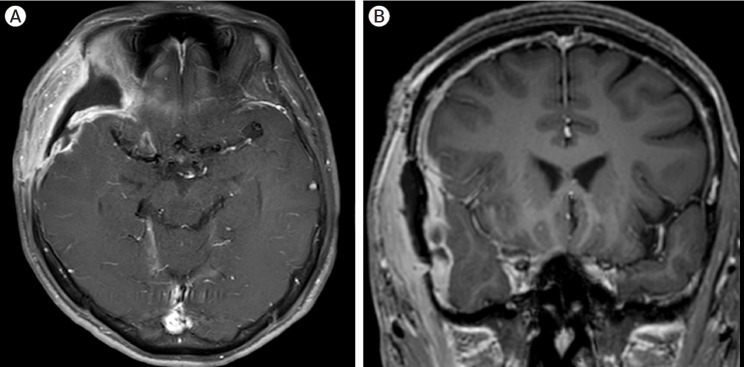

Objective: We evaluated the role of subgaleal closed suction drains in postoperative epidural hematoma (EDH) and wound complications following pterional craniotomy for cerebral aneurysm.

Methods: We reviewed 5,280 pterional craniotomies performed on 5,139 patients between January 2006 and December 2020. A drain was placed subgalealy and tip of drain was positioned between the bone flap and the deep temporalis. 1,637 cases (31%) had a subgaleal suction drain. We analyzed demographic and clinical variables related to EDH requiring evacuation and wound complications in patients with and without drains. Univariate and multivariate logistic regression analyses were performed to determine the associated risk factors.

Results: Fourteen cases (0.27%) of EDH requiring evacuation and 30 cases (0.57%) of wound complications were identified. Univariate analysis found that drain insertion, subarachnoid hemorrhage (SAH), and operation time were associated with EDH, while drain insertion, SAH, male gender, older age, and longer operation time were associated with wound complications. Multivariate analysis found no significant association between drain use and EDH (OR=1.62, p=0.402) or wound complications (OR=1.45, p=0.342).

Conclusions: Routine use of subgaleal closed suction drains may not be necessary after pterional craniotomy, as drain insertion was not associated with a reduced risk of EDH requiring evacuation or wound complications.